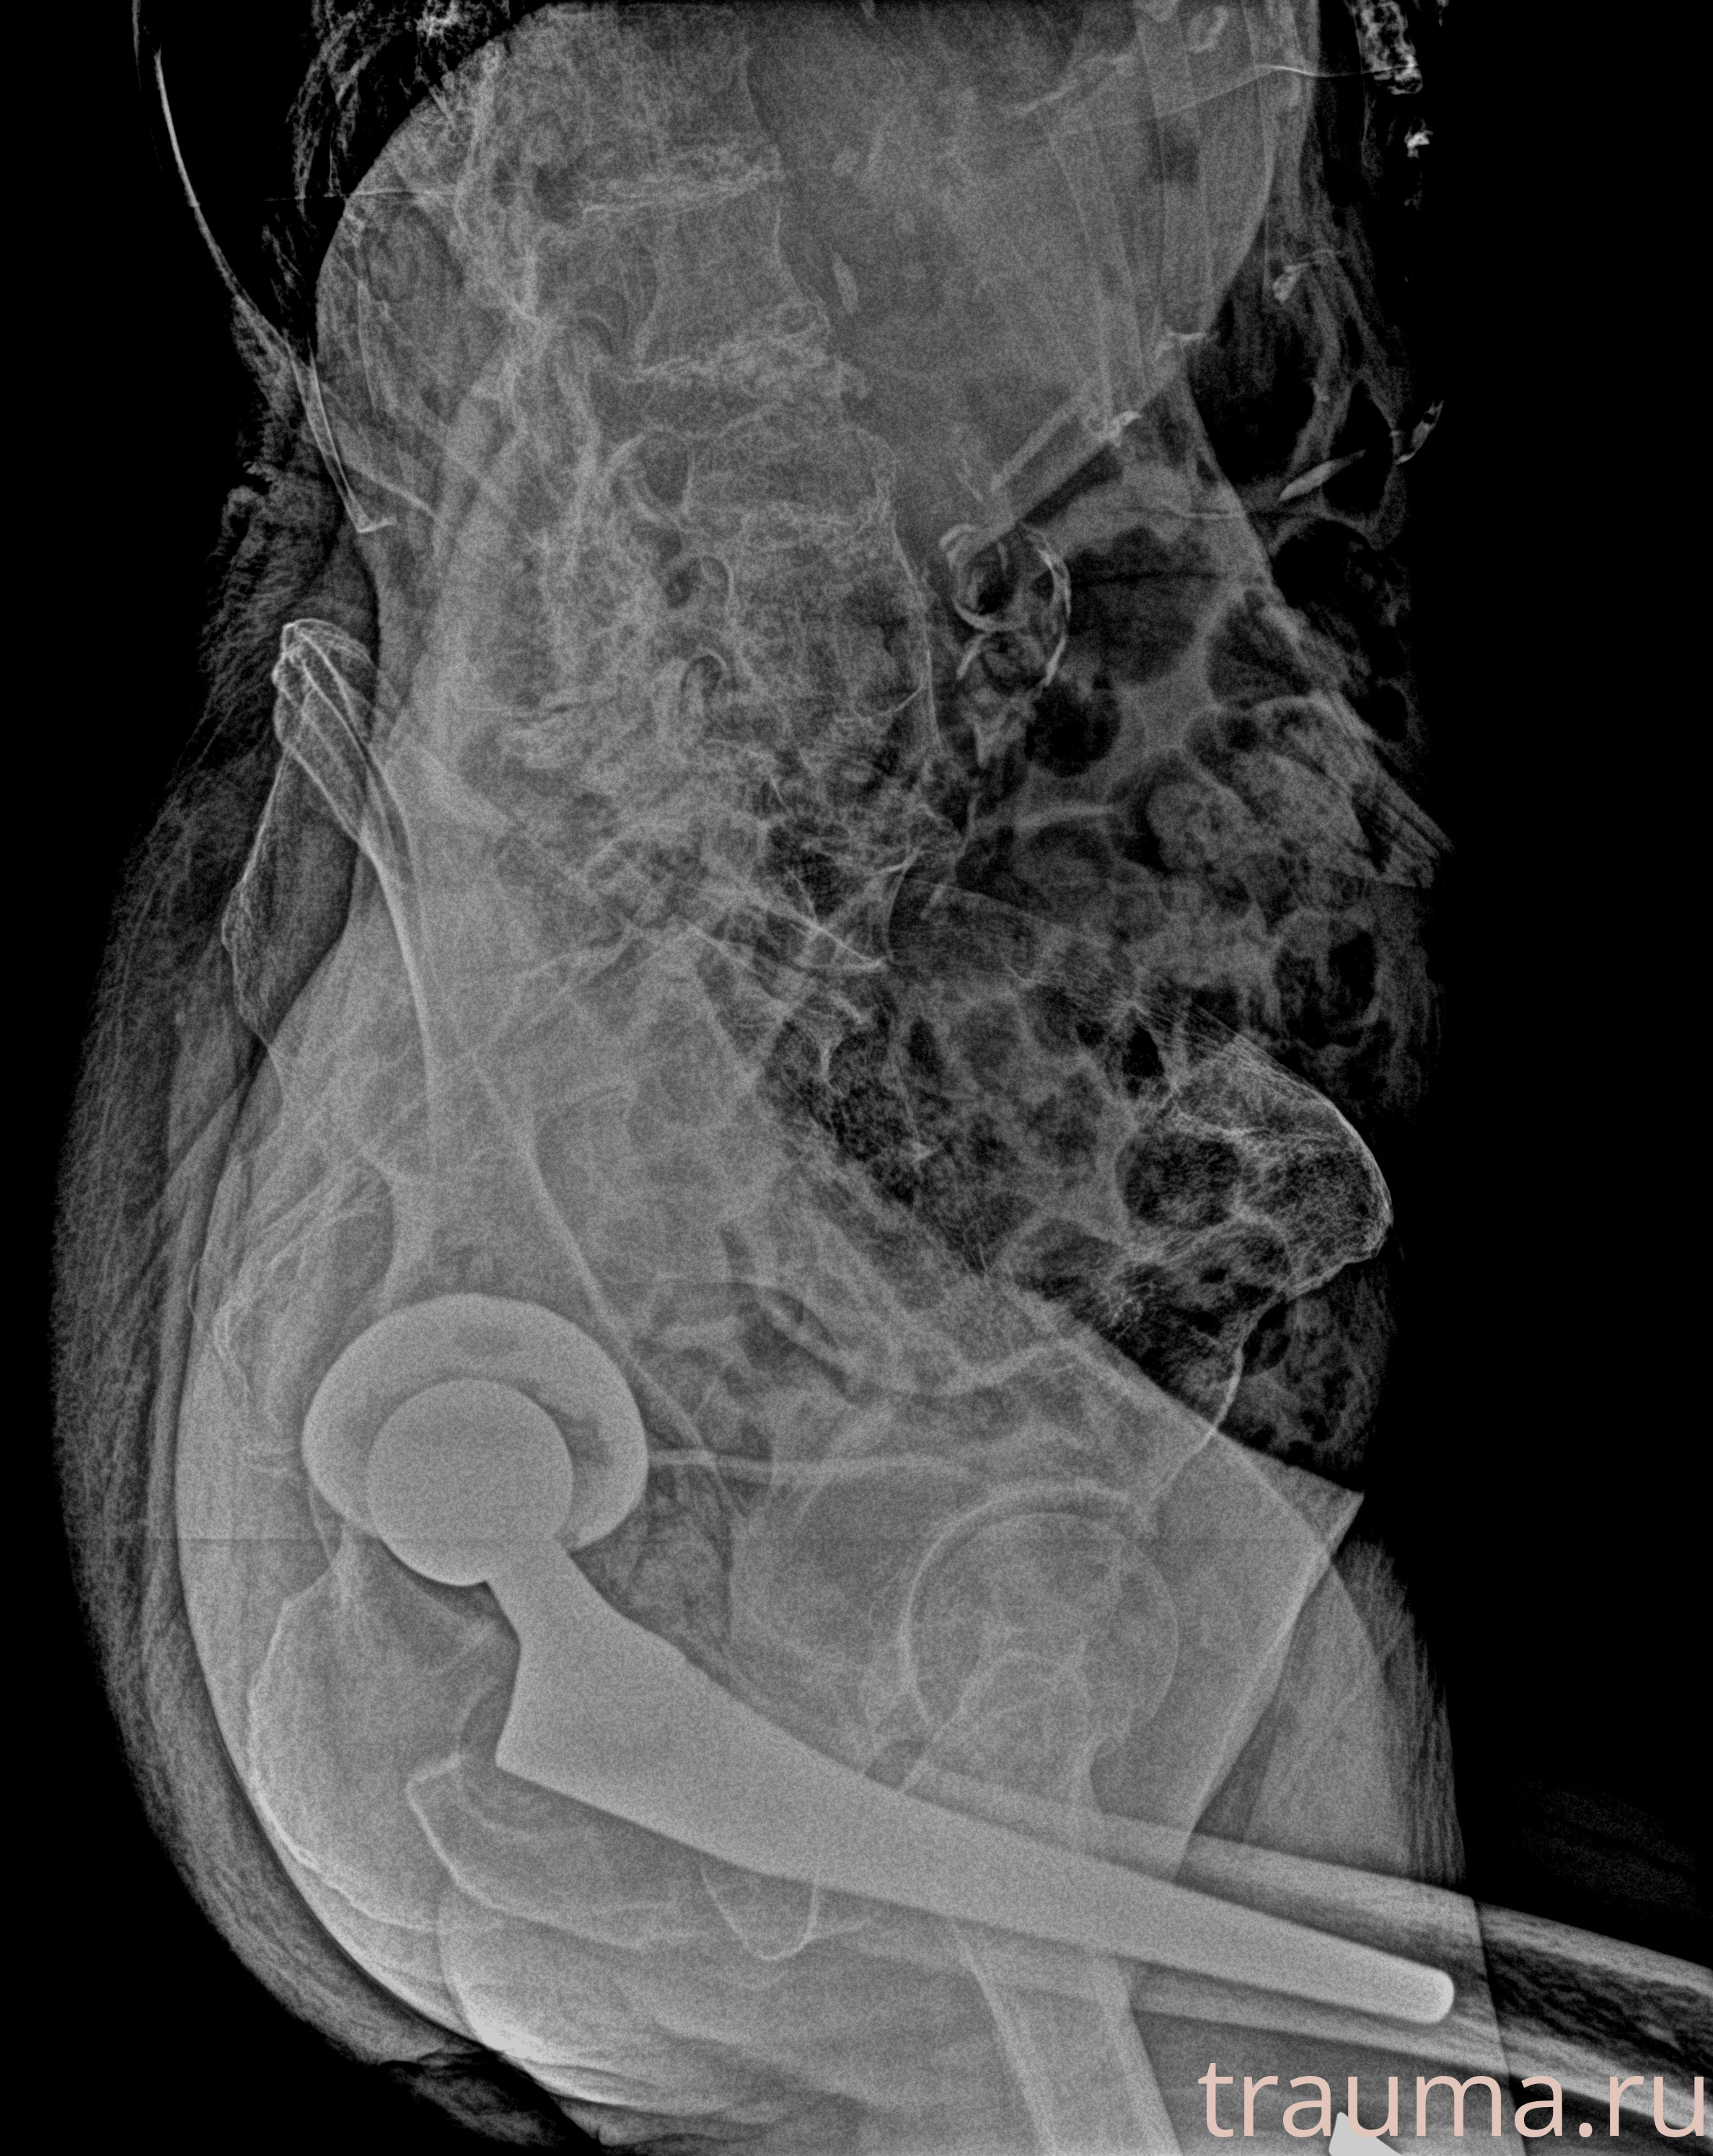

Рентген на дому: по вашему адресу приезжает врач-рентгенолог, травматолог-ортопед с мобильным рентгеновским аппаратом, проводит диагностику травмы или заболевания, делает необходимые рентгенограммы, дает рекомендации по дальнейшему лечению. Получить качественные снимки в домашних условиях возможно благодаря уникальной методике, разработанной МосРентген Центром для института  Склифосовского